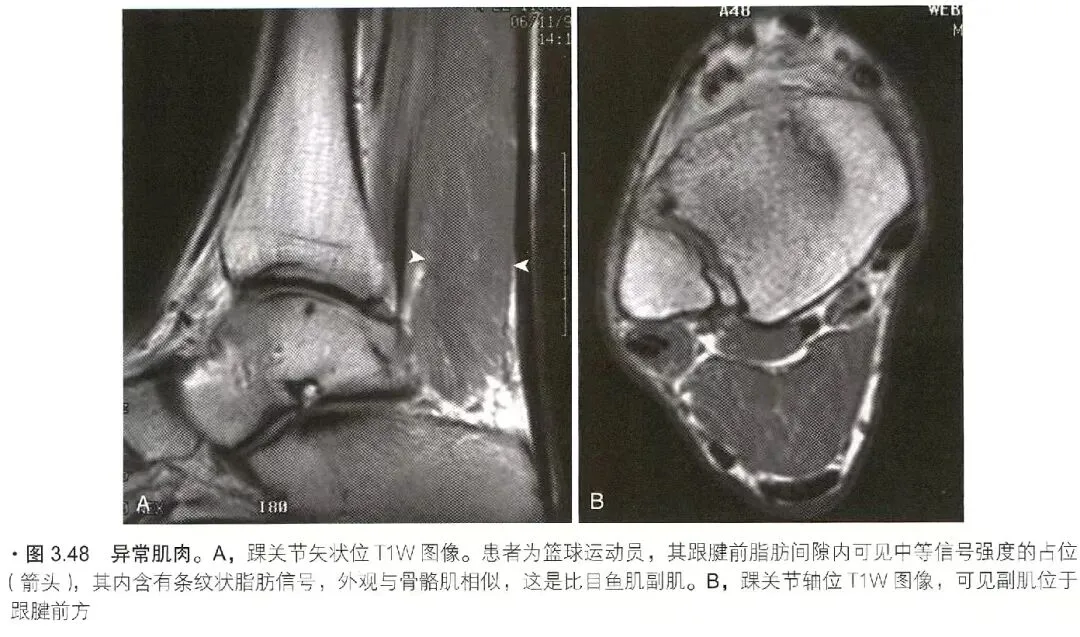

肌疝